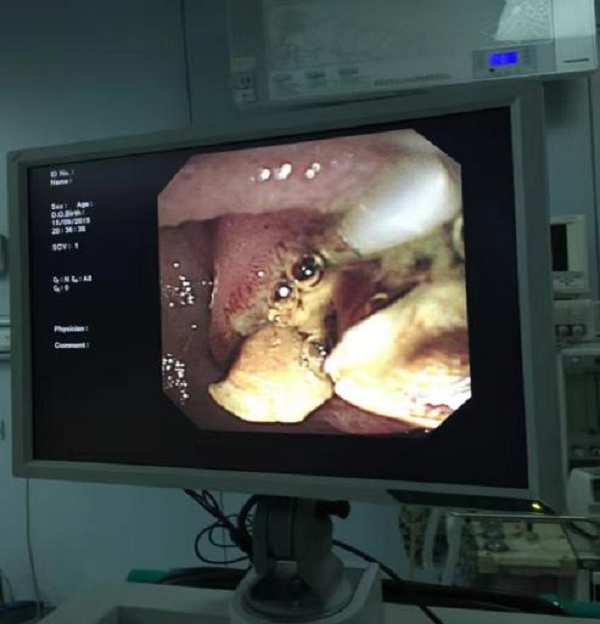

术中影像